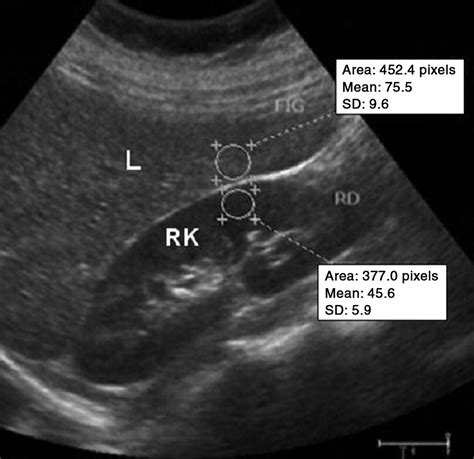

In the world of medical imaging, the liver is typically used as the "benchmark" for brightness. Healthy liver tissue has a specific texture and gray-scale appearance known as isoechogenicity. When an ultrasound technician scans the liver, they compare its brightness to the nearby kidney cortex and the spleen. If the liver appears brighter, darker, or more grainy than normal, it signals a change in the internal composition of the organ. The echogenicity of the liver is a direct reflection of how much sound energy is bouncing back to the transducer, which changes based on the presence of fat, fibrous tissue, or cellular swelling.

Radiologists categorize the liver's appearance into three primary grades based on how the echoes are reflected. Recognizing these variations is the first step in identifying underlying liver disease:

• Hyperechoic Liver: This occurs when the liver appears brighter than the kidney. It is the most common indicator of hepatic steatosis, or fatty liver disease, where fat cells infiltrate the liver tissue.

Mild Fatty Liver Increased (Mildly Hyperechoic) Slightly brighter than kidney

Severe Fatty Liver Markedly Hyperechoic Bright, poor visualization of vessels